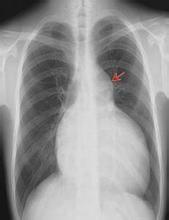

(2)詢問病史及各項檢查結果,如心電圖、超聲心動圖、胸片、CT、MRI等,根據臨床要求設計造影方法。